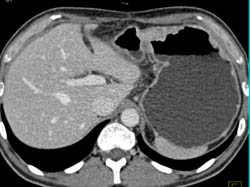

Perforated Gastric Tumor- Gist With Stent